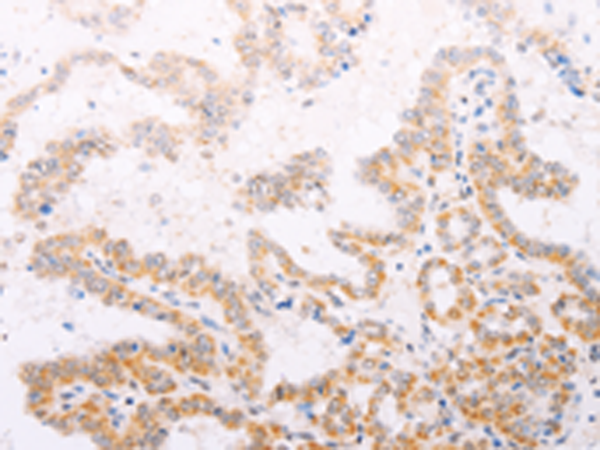

分类: 科研抗体货号: P07712别名: NR1I1; PPP1R163应用: IHC反应种属: Human, Mouse, Rat